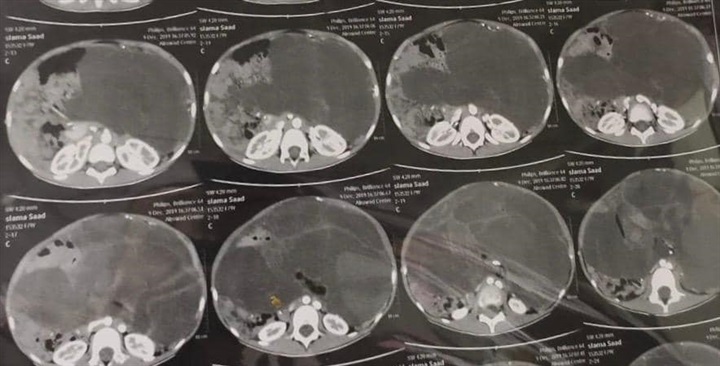

أعلن الدكتور طارق الجمال رئيس جامعة أسيوط عن نجاح فريق طبي بمستشفى الأطفال الجامعي من استئصال ورم يزن 8 كجم من بطن طفلة تبلغ من العمر 9 سنوات من محافظة أسوان.

ومن جانبه أوضح الدكتور ماهر مختار مدير مستشفى الأطفال الجامعي بأسيوط أن أهل الطفلة لاحظوا وجود انتفاخ بشكل غير طبيعي في البطن مما استدعى توجههم لمحافظة أسيوط لفحص الحالة بمعرفة أحد الأساتذة المتخصصين وهو ما قام به الدكتور محمد مدحت نصر مدرس الجهاز الهضمي والذي أجرى عدداً من الفحوصات التي أثبتت وجود ورم ضخم في بطن الطفلة يستدعى استئصاله.

وأضاف الدكتور طارق صبره مدرس واستشاري الجراحة العامة وجراحة الأطفال، أن حالة الطفلة كانت تستدعى جراحة دقيقة لاستئصال الورم بشكل كامل والذي كان يشمل معظم محيط البطن وناشئ من المبيض الأيسر وهو ما تم شرحه لأسرة الطفلة للموافقة على إجراء العملية حيث تم تشكيل فريق طبي تحت رعاية الدكتور إبراهيم على رئيس وحدة جراحة الأطفال بالمستشفى وبرئاسة الدكتور طارق صبره ويضم الدكتور حسين إبراهيم فرح المدرس المساعد بقسم جراحة الأطفال والطبيب أحمد كامل الطبيب المقيم بالقسم إلى جانب فريق التخدير والذي يضم الدكتورة سهام معين الأستاذة المساعدة بقسم التخدير والدكتور أيمن عبد الخالق المدرس بالقسم والطبيب محمد سالم حيث نجح الفريق الطبي في استئصال الورم بالكامل فى جراحة استغرقت ثلاث ساعات مع المحافظة على المبيض والأنبوبة الرحمية وتعافى الطفلة بشكل كامل.